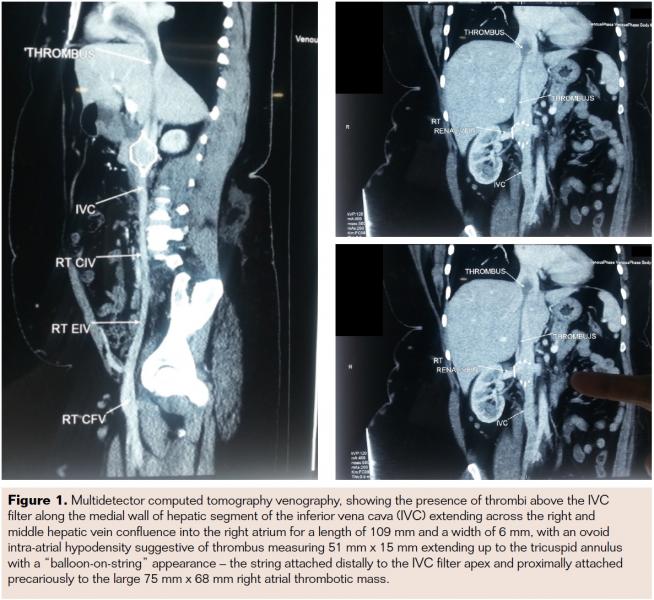

A 25-year-old female presented to the emergency department with shortness of breath and palpitations. She was referred with a possible diagnosis of right atrial myxoma, diagnosed on transthoracic echocardiography. Her past medical records revealed a history of DVT – chronologically, an isolated incident not associated with any precipitating risk factor initially and subsequently, 2 incidents associated with pregnancy. Her family history indicated DVT in her mother and maternal aunt. Laboratory investigations, including clinical biochemistry and hematology, were within normal limits. Echocardiography revealed a large “ball-valve like” thrombus across the tricuspid valve with mild right atrial and right ventricular dilatation and mild pulmonary arterial hypertension. Computed tomographic (CT) pulmonary angiogram revealed thrombus in bilateral lower lobe branches. Whole-abdomen CT with contrast was performed and showed linear eccentric filling defect in the IVC, extending from the IVC filter into the right atrium. A multidetector computed tomography (MDCT) venography confirmed the presence of thrombi with a “balloon-on-string” appearance (Figure 1). Thrombolysis was considered risky due to the potential for catastrophic release of thrombus from the IVC filter into the pulmonary artery, leading to pulmonary embolism because of the long and thin “string-like” attachment. Thrombosuction also carries the risk of breaking loose the “balloon clot” into the pulmonary arterial system. Thrombolysis with recombinant tissue plasminogen activators has the potential of dislodging the thrombus (balloon component) with catastrophic consequences. Hence, surgical treatment was considered the ideal option and the removal of the thrombus was done under deep hypothermic total circulatory arrest (DHCA). The postoperative period was uneventful, echocardiogram showed no evidence of thrombus, and the patient was discharged.